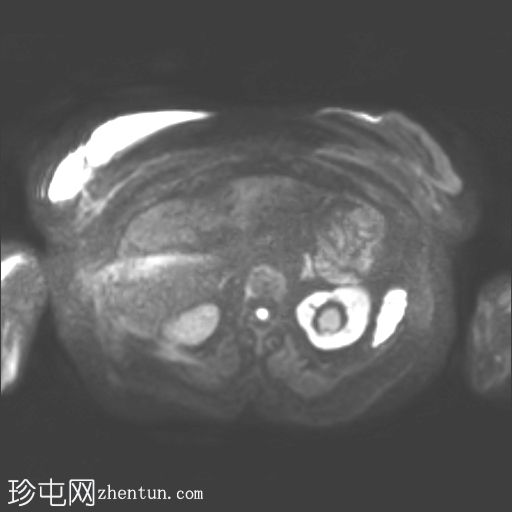

轴位

T2

子宫呈U形,宫底轮廓消失,宫底突出至扩张的阴道内,宫颈位于内翻的宫底上方(II级子宫内翻):

宫底处可见阴道内可见边界不清、分叶状实性肿块,明显扩张阴道壁,阴道壁完整。

肿块最大轴向及头尾径约为 9.7 x 9.6 x 9.5 cm,T1 加权像呈低信号,T2 加权像呈中/高信号,伴有扩散受限和不均匀增强。

左侧附件复合体病变,包含实性和囊性成分,轴向径约为 5.3 x 4.7 cm。实性成分 T1 加权像呈低信号,T2 加权像呈中信号,伴有扩散受限和增强。

轴位MRI:可能显示靶环状或同心环状结构,提示子宫内膜存在不同层次。

MRI有助于确定病因,尤其是在非产褥期病例中(例如,子宫肌瘤、子宫肌肉瘤或子宫内膜恶性肿瘤),如本例所示。